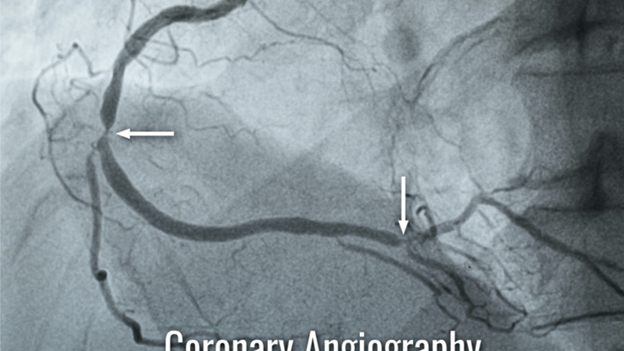

So, what’s a coronary angiogram all about? Simply put, it’s a special X-ray used to check whether your heart’s blood vessels are doing their job right. This helps spot any blocked or narrowed areas that may lead to heart issues. Think of it as a peek inside your heart’s expressway.

During this process, a small, flexible tube called a catheter is placed inside your large groin or wrist artery and maneuvered to your heart. Then, a special dye that shows up under X-ray is squirted in through the tube. This dye lights up your arteries on the screen, helping doctors see exactly where any problems might be.

After the doctor inserts the catheter, they thread it up to your heart. The special dye helps highlight your arteries on X-ray monitors. Doctors will review these images to see if any areas are narrowed or blocked.